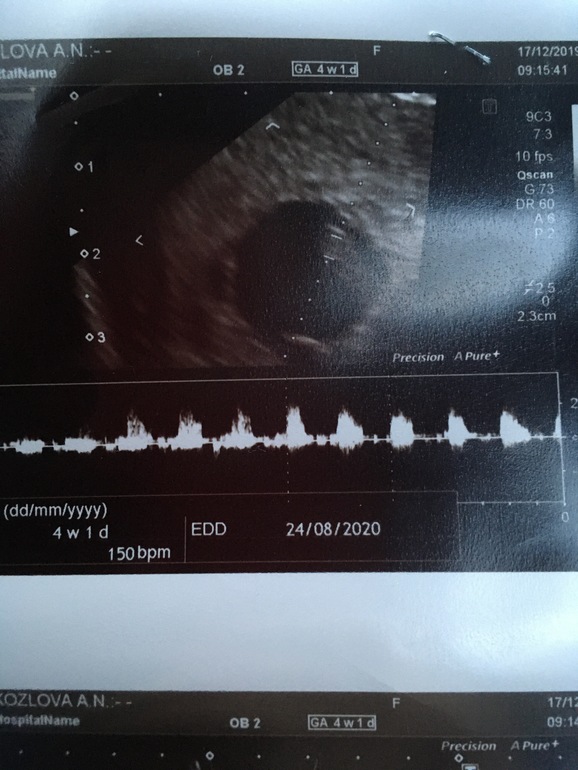

Наше второе УЗИ 17.12

Я тоже сегодня первый раз на УЗИ ездила,ровно в 8 недель,состояние ,как и у вас было)Расплакалась,когда врач включила сердечко послушать) Лёгкой вам беременности!

Поздравляю )))) биение сердечка малыша - самый волшебный звукРастите здоровенькими)